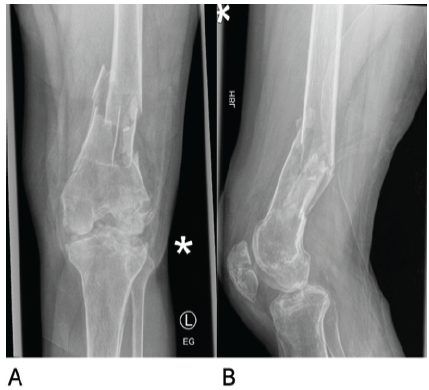

After experiencing persistent knee pain, swelling, and reliance on a crutch for mobility, he was referred back to the orthopedic outpatient clinic. Eight months after the removal of implants, examination demonstrated minimal tenderness but substantial joint effusion and an inability to sustain SLR. This raised the possibility of a partial quadriceps muscle rupture. Inflammatory markers were normal (white cell count 5.3 × 109/L, CRP 6 mg/L). An MRI performed at that time excluded a quadriceps rupture, noting joint effusion, synovitis, and degenerative changes in the tibial plateaus and femoral condyles. Unfortunately, the absence of pain, normal inflammatory markers, and lack of systemic features of infection were falsely reassuring, and MRI changes were attributed to post-traumatic degenerative changes. He was referred for quadriceps strengthening physiotherapy with an emphasis on gradual progression. The patient returned with knee pain, joint effusion, and ongoing limited knee extension 3 months later. Repeat blood work again showed no acute inflammatory changes (ESR 18 mm/h, white cell count 5.6 × 109/L, CRP 7 mg/L). A subsequent MRI (Fig. 2) revealed extensive tricompartmental knee arthritis with joint space narrowing, chondral loss, subarticular geodes, and significant subchondral bone marrow edema, along with a collection in the gastrocnemius.

Figure 2: Magnetic resonance imaging scan of the left knee (a) Sagittal view of the medial tibial joint space. (b) Coronal view of the centre of the knee joint. (c) Sagittal view of the lateral tibial plateau

These findings, along with accompanying effusion and synovitis, raised the possibility of infective arthropathy.